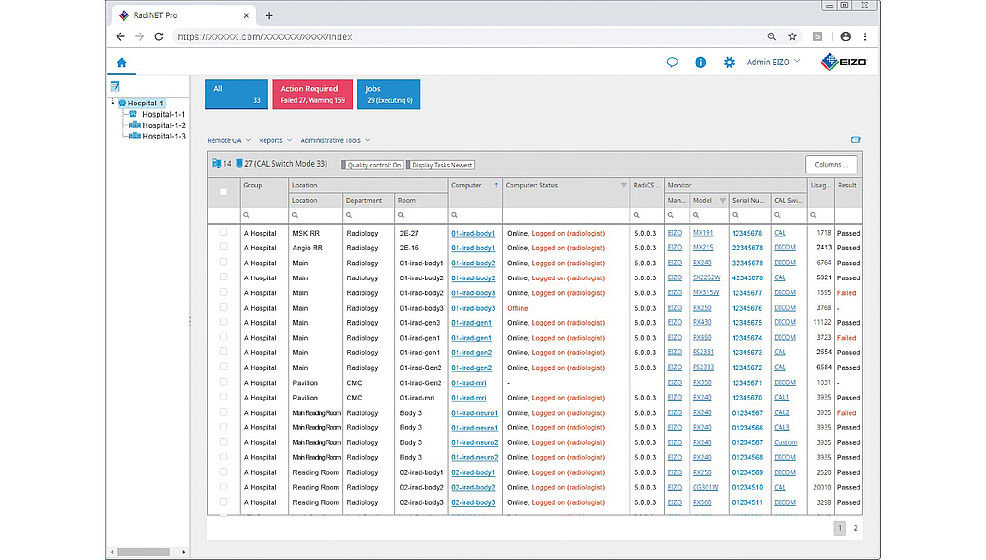

Zarządzanie jakością monitorów w całym szpitalu

RadiNET Pro pozwala centralnie zarządzać wszystkimi monitorami podłączonymi do sieci szpitalnej. Wygodna aplikacja oparta na przeglądarce zapewnia łatwy dostęp do wszystkich potrzebnych informacji. Z jej pomocą administrator może przeprowadzić lub zaplanować kontrolę jakości z dowolnego miejsca w szpitalu. RadiNET Pro daje wgląd w dane takie jak nazwa modelu i czas pracy poszczególnych monitorów czy podłączone komputery i karty graficzne. W razie potrzeby szczegółowe informacje o każdym monitorze można skonsolidować w postaci raportu.